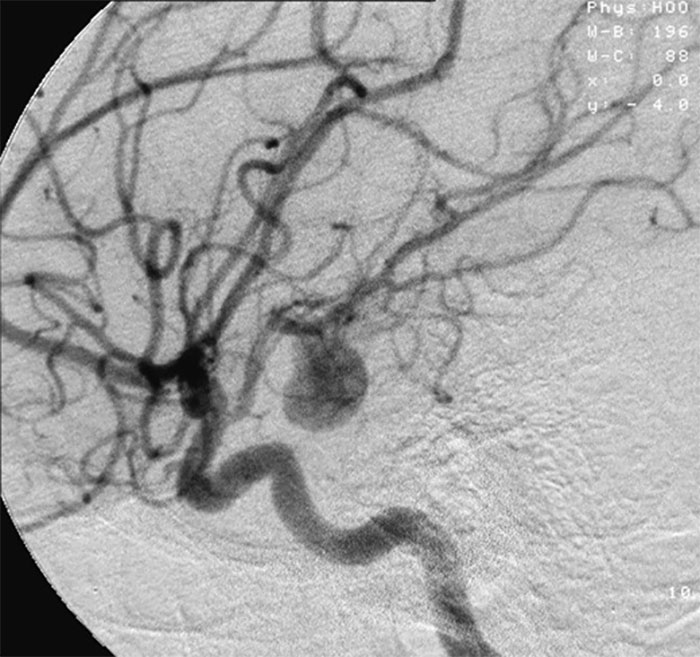

Podrías caer muerto al instante por una hemorragia cerebral/aneurisma y no tener ningún signo de alarma previo. Un segundo estás perfectamente bien, y al siguiente estás muerto.